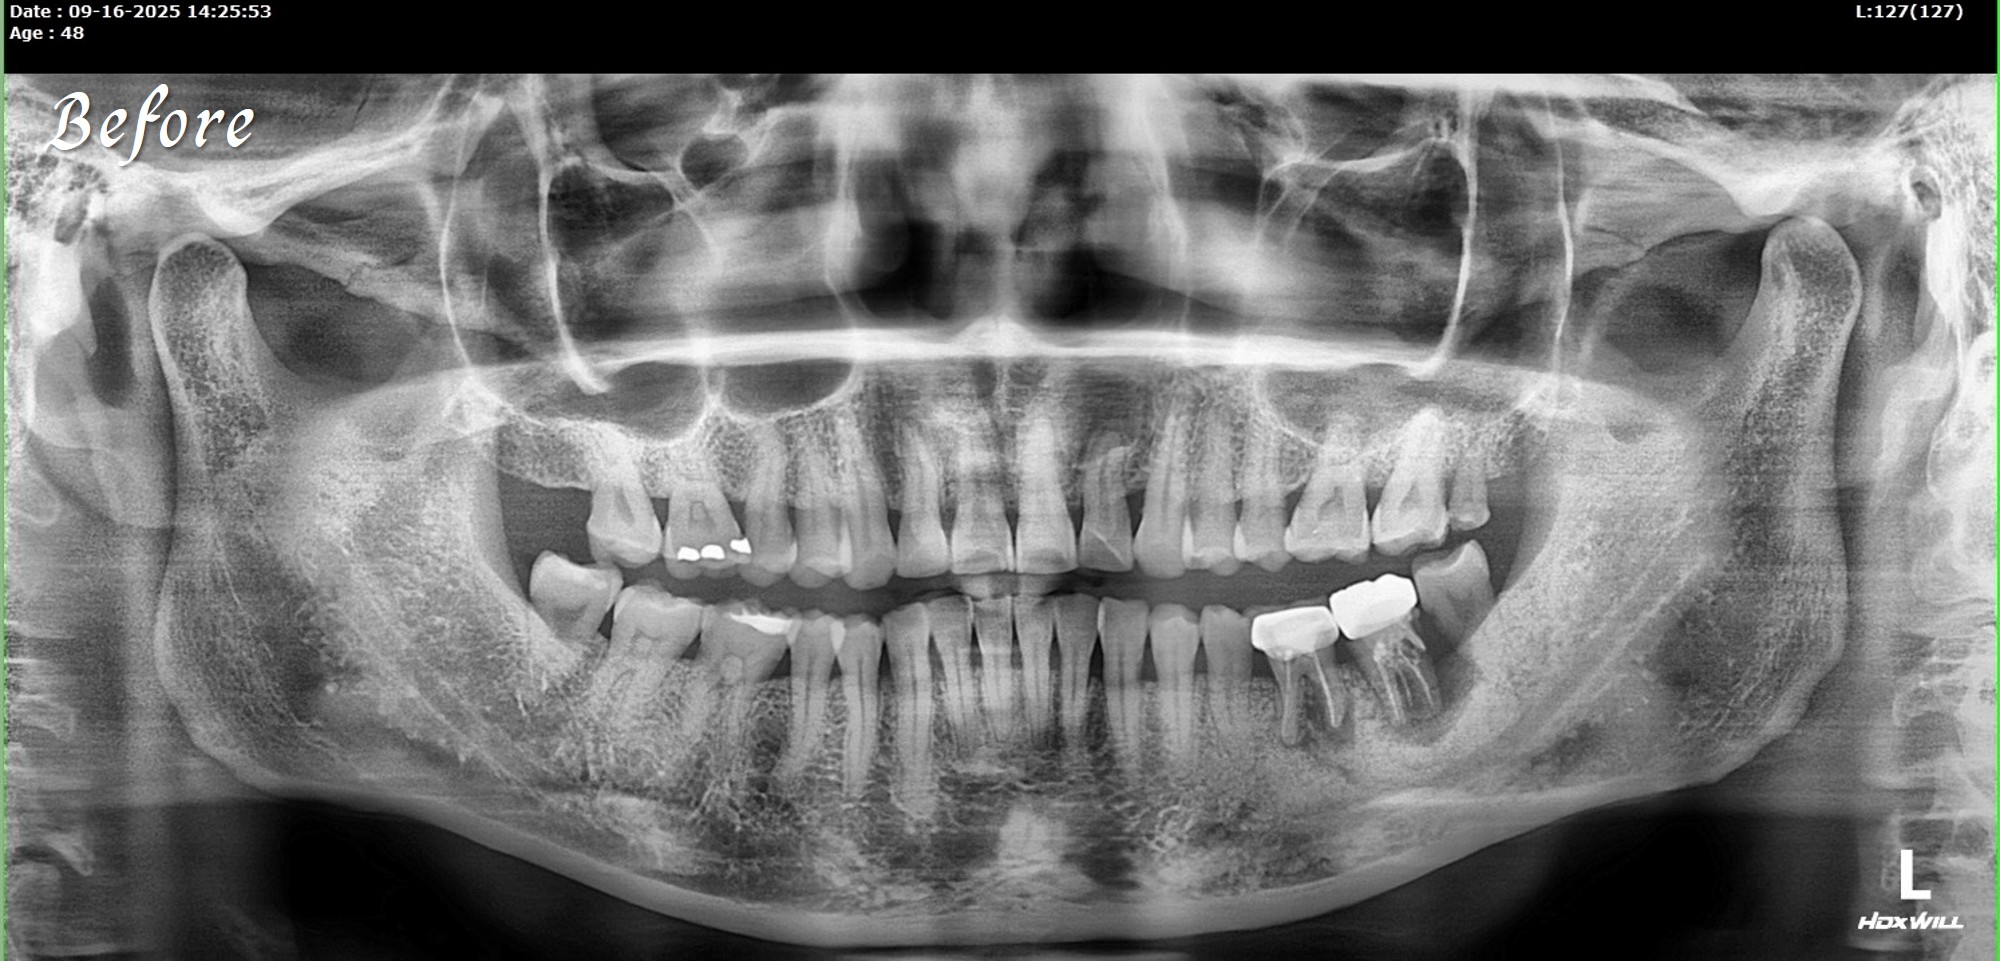

精奈創一鑽植牙系統團隊|3.5個月完成的植牙案例

一位初診新患者,陳博士評估後進行治療。

植牙後約3.5個月骨整合完成,骨頭穩定生長良好。

這樣的恢復速度,與Ezechbone的特性有關,

但最重要的是要有良好的primary stability。

若以一般傳統流程,往往需要先拔牙後等待數月,

再補骨、放人工膜,等待約10 個月左右,

之後還得再取出人工材料才能進行植牙,

整個療程動輒一年以上,空窗期長,變數也多。

陳博士的治療方式,手術過程中不使用人工膜,

僅以可吸收縫線(chromic gut suture))完成縫合。

植牙當天,scan body掃描就同步完成,流程一次到位。